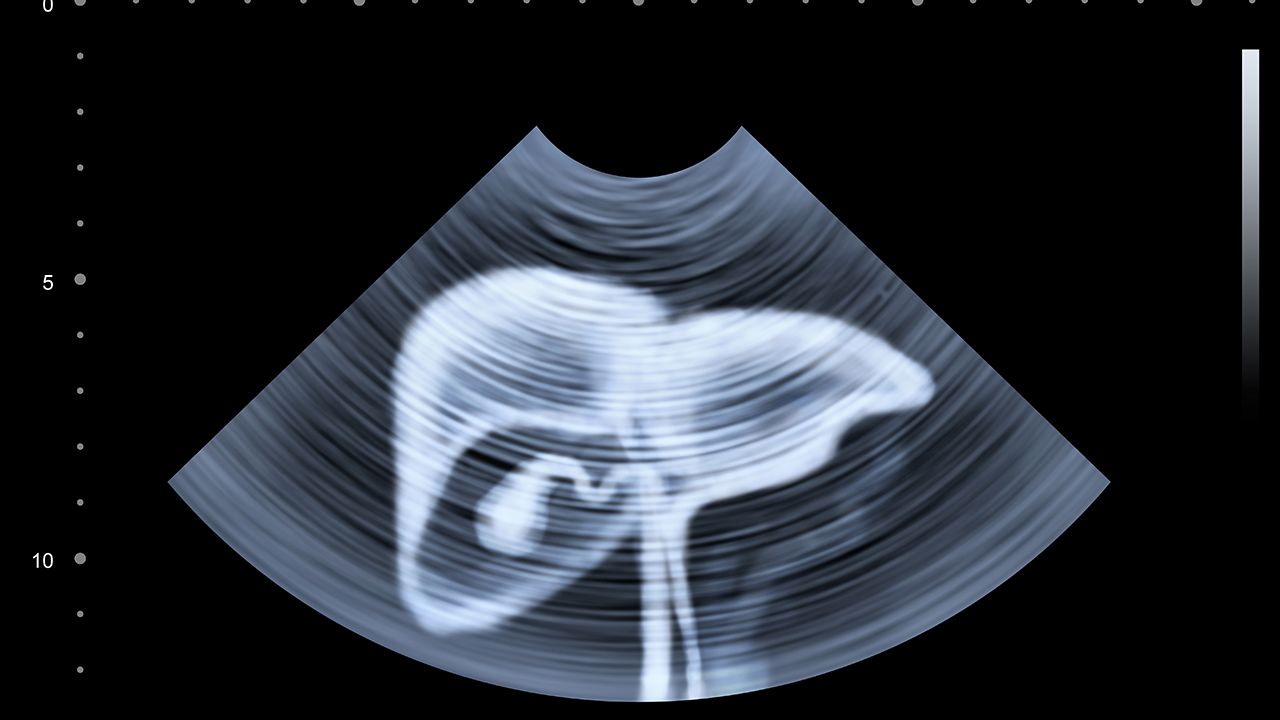

肝癌是一種常見(jiàn)的惡性腫瘤,其發(fā)病原因復雜,包括病毒性肝炎、肝硬化、長(cháng)期酗酒、黃曲霉素暴露等。早期肝癌癥狀不明顯,容易被忽視,因此定期體檢對于高風(fēng)險人群尤為重要。